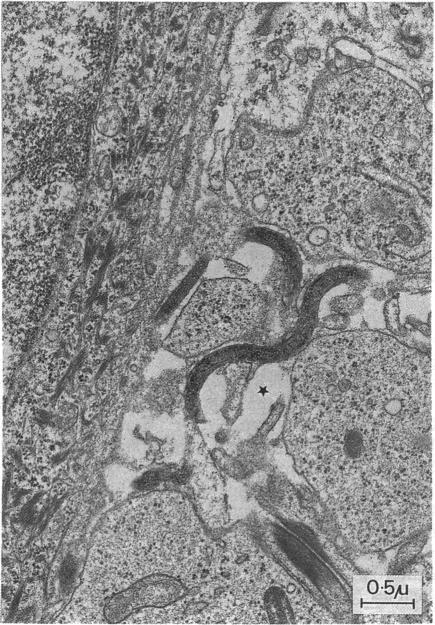

Biopsy material originating from skin lesions in ten young children suffering from early infectious yaws in Indonesia, and rabbit testicular tissue inoculated with T pertenue. Human skin as well as rabbit testicular tissue was examined by means of conventional electron microscopy.

In human skin, treponemes were found in interepidermal spaces in 5 out of 10 specimens. In two of five positive specimens, treponemes were also seen in the dermis. In one out of five specimens from rabbit testicular tissue a profusion of treponemes was found lying in the interstitial myxomatous tissue. Microorganisms showed no adhesion to fibroblasts.

This ultrastructural study of T pertenue demonstrated the scarcity and focal distribution of treponemes in tissue and did not reveal any morphological differences from the Gauthier strain of T pertenue. No differences from the ultrastructure of T pallidum were observed either.

取自印度尼西亚10名患有早期感染性雅司病的幼儿皮肤病变的活检材料,以及接种了品他密螺旋体的兔睾丸组织。采用传统电子显微镜检查人皮肤和兔睾丸组织。

在人皮肤中,10个标本中有5个在表皮间隙发现了密螺旋体。在5个阳性标本中的2个中,真皮中也可见密螺旋体。在兔睾丸组织的5个标本中的1个中,在间质黏液瘤样组织中发现大量密螺旋体。微生物未显示与成纤维细胞的黏附。

本品他密螺旋体的超微结构研究表明,密螺旋体在组织中的数量稀少且呈局灶性分布,与品他密螺旋体的高蒂埃菌株在形态上没有差异。也未观察到与梅毒螺旋体超微结构的差异。